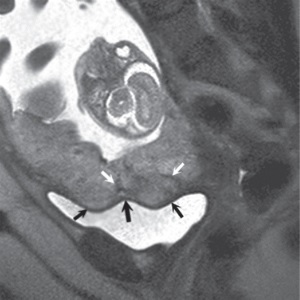

FIGURE 4.1 Normal placenta on magnetic

resonance imaging (MRI) in the late second trimester. (a) On

T1-weighted images, the placenta is homogeneous and

isointense to muscle throughout pregnancy. (b) On

fat-suppressed T2-weighted images, the placenta is fairly

homogeneous and bright with darker thin septa and vessels

seen. Note both the inner (fetal) surface (white arrows, a;

black arrows, b) and outer (maternal) surface (black arrows,

a; white arrows, b) of the placenta are smooth. There is no

placenta previa in this case as the anterior placenta is

remote from the cervix (“c,” a and b). Later in the third

trimester, the inner surface may become lobulated in a

regular pattern related to the cotyledons; however, the

outer maternal surface remains smooth, flowing the expected

contour of the uterine wall.